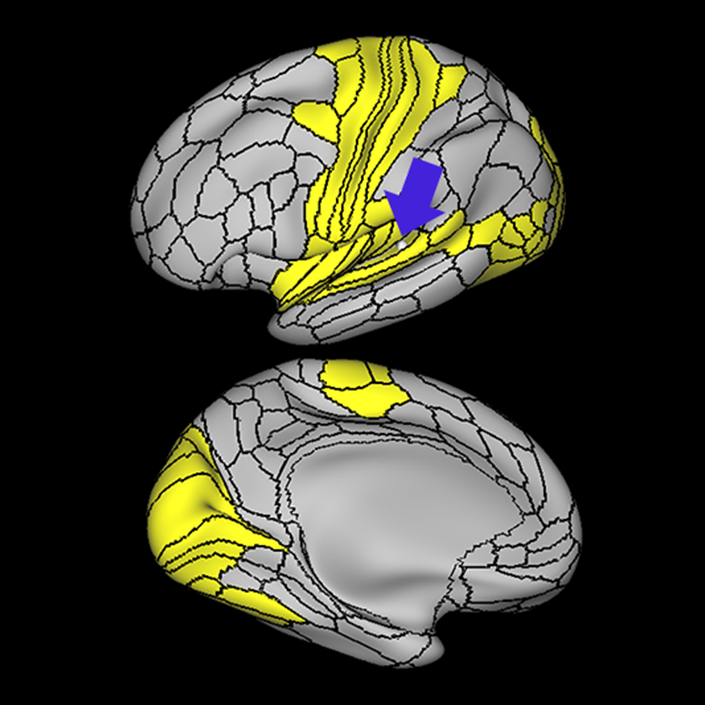

ᐅ SummaryArea 55b: part of the premotor areas. Relatively uncharacterized regions. In 1956, one of the only studies to characterize this regions concluded that the area played a role in language processing. ᐅ Where is it?Area 55b is located on the anterior half of the precental gyrus, approximately half way down its length along the convexity, just inferior to FEF. It also forms the adjacent floor of the precentral sulci and straddles slightly onto the posterior edge of the middle frontal gyrus. ᐅ What are its borders?Area 55b borders area FEF superiorly and PEF and area 6v inferiorly. Area 4 is its posterior border and areas 8AV and 8C form its anterior border across the precentral sulcus. ᐅ What are its functional connections?Area 55b demonstrates functional connectivity to area 4 in the motor strip, areas SCEF and SFL in the premotor areas, areas IFSp, IFJa, 8AV, 44, 45, and 47L in the lateral frontal lobe, areas STSda and STSdp in the temporal lobe, areas PSL and STV in the posterior opercular cortices, and area TPOJ1 in the lateral occipital lobe. ᐅ What are its white matter connections?Area 55b is structurally connected to the contralateral hemisphere and the superior longitudinal fasciculus. Contralateral connections course through the body of the corpus callosum to 6ma, 6a and 6mp. Connections with the superior longitudinal fasciculus connect 55b to parcellations PHT and PFm, and this tract terminates eventually in the temporal lobe at TGd. Local short association fibers connect with 8Av, 8C, IFJp, 3a, 3b and PEF. ᐅ What is known about its function?Area 55b is a relatively uncharacterized region. In 1956, one of the only studies to characterize this region concluded that the area played a role in language processing. |

A: lateral-medial

B: anterior-posterior

C: superior-inferior

DTI image |